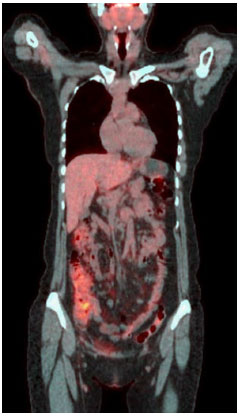

Quando a paciente procurou nosso serviço, ainda apresentava constante alteraçoes do hábito intestinal, odinofagia, cefaleia, lesoes eritematosas em face, mialgia em coxas e pernas e poliartralgia em ombros, punhos e tornozelos. A paciente negava perda de peso e se queixava de esquecimento e estresse emocional frequentes. Nao referia antecedente familiar de doenças autoimunes e neoplasias. O pai havia falecido por infarto agudo do miocárdio e a mae estava viva, com problemas cardíacos e vasculares. A paciente foi novamente internada para investigaçao. Neste momento a paciente apresentava leucocitose e neutrofilia, além de elevaçao de provas inflamatórias de fase aguda. Para que causas infecciosas, inflamatórias ou neoplásicas fossem excuídas, foi realizado PET-Scan (tomografia por emissao de pósitrons) de corpo inteiro (Figura 1). A partir desta imagem foi realizado colonoscopia para se descartar doença inflamatória intestinal. Com a ausência de alteraçoes na colonoscopia e por nao haver causa infecciosa ou neoplásica que justificassem o quadro da paciente, foi aventada a hipótese de doença autoinflamatória sistêmica, provavelmente febre familiar do Mediterrâneo e introduzido empiricamente colchicina na dose de 1,5 mg/dia. Após dois dias de tratamento, houve normalizaçao do quadro clínico e das provas inflamatórias (Tabela 1).

Para a definiçao desta síndrome clínica, a primeira coisa a fazer é a definiçao clínica. Neste caso, a paciente apresentava-se clinicamente com: febre, dor abdominal recorrente (peritonite), diarreia, artralgia e rash cutâneo similar à erisipela. Partindo destas manifestaçoes, se nao pensarmos inicialmente em doença autoinflamatória, o quadro é inespecífico e a primeira coisa a fazer é excluir ou confirmar outros diagnósticos. Para isto, faz-se necessário comprovaçao de que a síndrome em investigaçao cursa com "surtos estéreis". Assim, realizamos a investigaçao diagnóstica para afastar os eventuais diagnósticos diferenciais e comprovar de fato que a paciente tinha aumento de provas inflamatórias, de forma intermitente. Neste caso a paciente foi internada e excluída doenças infecciosas (surtos curtos sem evidência clínica de infecçao), doenças neoplásicas (análise de PET-Scan de corpo inteiro excluiu hipercaptaçao de locais suspeitos) e autoimunidades, pela ausência de autoanticorpos e ausência de quadro clínico compatível.

A demonstraçao de atividade inflamatória em surto é essencial. Ela pode ser sistêmica ou local. Quando em doenças sistêmicas, pode ser feita através de dosagens séricas de proteína C-reativa, velocidade de hemossendimentaçao, ferritina sérica, dosagem sérica de substância amiloide e, até mesmo, com dosagem de pool de citocinas12. A atividade inflamatória local pode ser aferida em cada sistema13-16, podendo-se demonstrar atividade inflamatória no liquor (celularidade aumentada - neutrofílica ou linfocítica - com proteinorraquia), dosagem de calprotectina fecal (evidência laboratorial de atividade inflamatória neutrofílica), dosagem de proteínas em derrames cavitários e, por fim, através da biopsia tecidual com demonstraçao de que a manifestaçao inflamatória é decorrente de células da imunidade inata. Eventualmente, a biopsia tecidual é necessária e espera-se encontrar infiltrados predominante neutrofílico com ou sem vasculite15. Neste caso, partindo deste raciocínio, a paciente apresentava a síndrome clínica de febre recorrente, pois conseguimos comprovar atividade inflamatória em surtos (PCR e VHS elevados na crise e normais nos períodos intercrises); ausência de doença autoimune clássica (ausência de manifestaçao clínica típica e autoanticorpos negativos); o PET-Scan mostrando captaçao peritoneal difusa, sugestivo de peritonite, foi de extrema utilidade para afastar hipóteses neoplásicas e infecciosas17,18, associado à colonoscopia com biopsias seriadas sem alteraçoes inflamatórias no anátomo-patológico, excluindo doença inflamatória intestinal19.